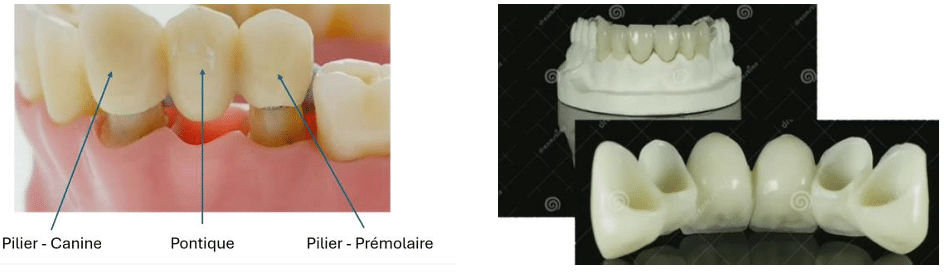

2) Bridges "dento-portés" // bridges "implanto-portés"

Les bridges dento-portés :

Le bridge (ou pont fixe) est une restauration prothétique plurale destinée à compenser une ou plusieurs pertes dentaires.

Il est constitué d’au moins deux éléments prothétiques solidarisés entre eux.

Le bridge est fixé de manière permanente à l’aide d’un ciment, assurant un collage définitif.

Les bridge implanto-porté :

Un implant peut permettre la réalisation d’une restauration unitaire ou plurale.

Grâce au bridge implanto-porté, il est parfois possible de poser deux implants pour remplacer trois dents, ce qui constitue une solution mécaniquement soutenable et économiquement plus avantageuse.